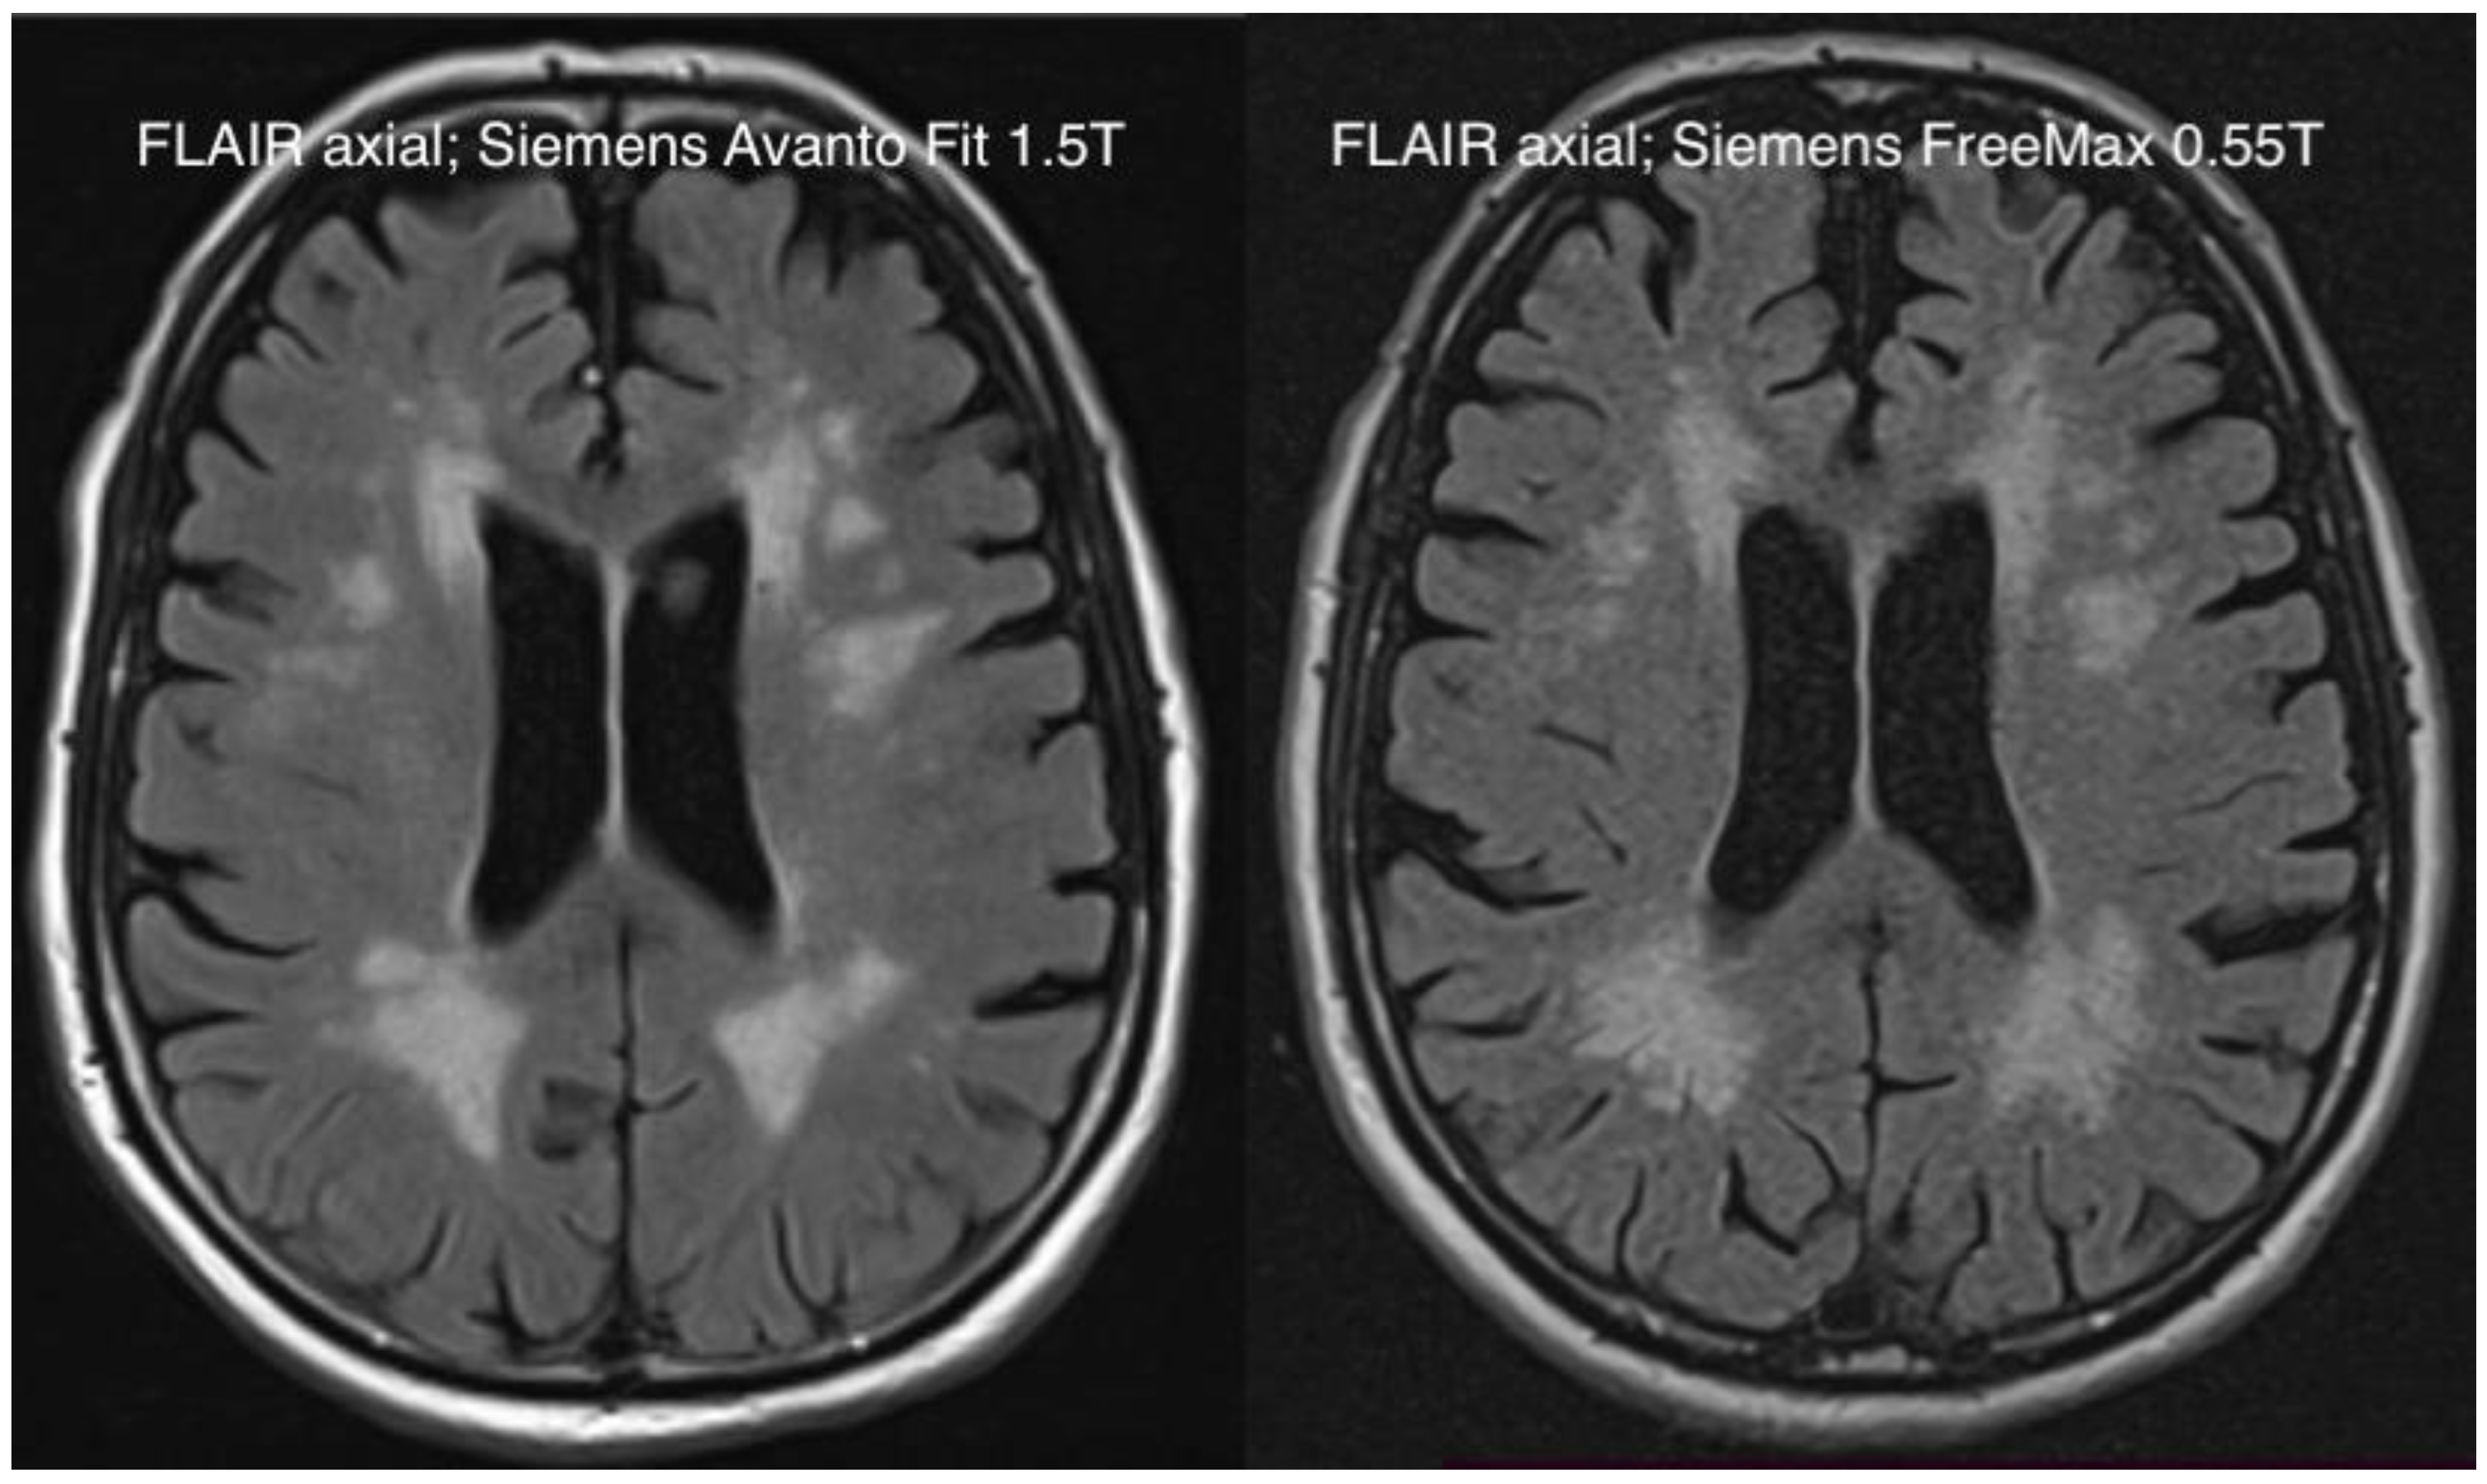

| Head | Fluid attenuated inversion recovery (FLAIR) axial | 1.5T | 8510 | 112 | 3 | 0.9 x 0.9 | 187 × 230 | 03:26 |

| 0.55T | 7780 | 96 | 3 | 1.3 × 1 | 209 × 230 | 05:28 | ||